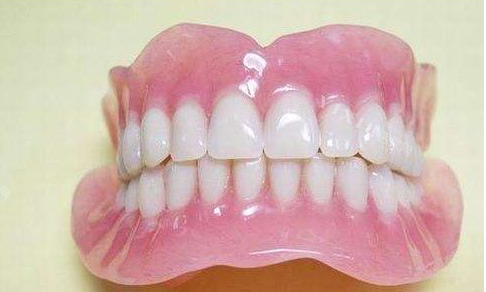

全口吸附性义齿,作为无牙颌患者的一种重要修复方式,近年来在口腔修复领域备受关注,被许多患者亲切地称为“第二副真牙”。那么,全口吸附性义齿究竟好不好呢?让我们从多个方面来详细探讨。

全口吸附性义齿,以其独特的吸附原理和良好的修复结果,成为了许多无牙颌患者的首要选择。它不仅能够修复患者的咀嚼功能,还能在一定程度上改善面部形态,提升患者的生活质量。

良好的吸附性:全口吸附性义齿通过特殊的基托设计和材料选择,能够在口腔内形成良好的吸附结果,确保义齿的稳定性和固位力。这对于无牙颌患者来说至关重要,能够有效避免义齿在使用过程中的松动和脱落。

舒适的佩戴体验:全口吸附性义齿的基托材质通常选用柔软、有弹性的材料,能够更好地贴合口腔黏膜,减少对口腔组织的刺激和压迫感。同时,其设计也充分考虑了患者的口腔结构和咀嚼习惯,使得佩戴更加舒适。

自然的外观结果:全口吸附性义齿在制作过程中,会充分考虑患者的面部形态和牙齿排列情况,力求达到较自然的外观结果。修复后的义齿不仅与患者的面部轮廓相协调,还能在一定程度上改善面部形态,让患者重拾自信笑容。